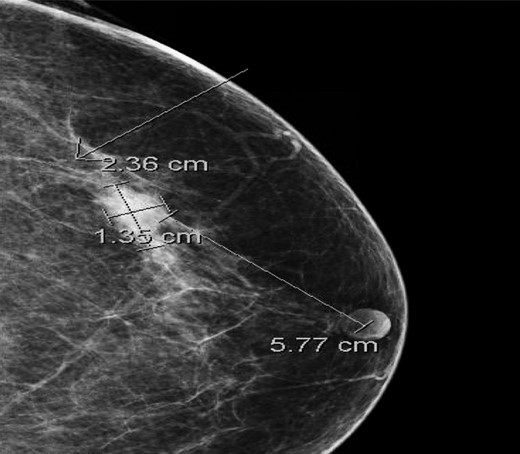

A 67-year-old female presented with a biopsy-proven and palpable IDC of the left breast. The patient had had two previous breast biopsies, both benign, over a decade ago. Her last mammogram from 2 years ago was without suspicious findings, and the patient had appreciated no lesion in the last 6 months of self-breast examinations. Her family history was significant for breast cancer in her mother, diagnosed at age 41. Her past medical history was otherwise notable for hypothyroidism, psoriatic arthritis, and an excised basal cell carcinoma of the chest wall. Mammography showed a 2.4 cm × 1.4 cm × 1.8 cm lobulated mass with indistinct margins in the left breast (Fig. 1).

Cranio-caudal view of mammogram showing a 2.4 cm × 1.4 cm × 1.8 cm lobulated mass with an indistinct margin in the left breast at 1 o'clock, 5.8 cm from the nipple.